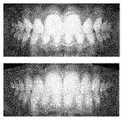

-[图3]图3示出了在步骤a)中获取的照片的一个示例,以及通过根据本发明的方法获得的修改图像的示例,该方法使用诸如图7中的记录进行训练;- [Fig. 3] Fig. 3 shows an example of a photograph obtained in step a), and an example of a modified image obtained by the method according to the invention, which is trained using recordings such as in Fig. 7;

-[图7]图7示出了用于训练模拟神经网络的记录的一个示例,以模拟事件“使用带有弓丝和托槽的正畸矫治器进行正畸治疗”,左侧图像和右侧图像分别在模拟神经网络的输入和输出处引入;-[Figure 7] Figure 7 shows an example of recordings used to train a simulated neural network to simulate the event "Orthodontic treatment using orthodontic appliances with arch wires and brackets", left image and right Side images are introduced at the input and output of the simulated neural network, respectively;

图7的左侧部分示出了在处理以分离牙齿轮廓之后的第一视图的一个示例。The left part of Figure 7 shows an example of a first view after processing to separate the tooth contours.

图7的右侧部分示出了在处理以分离牙齿轮廓之后的第二视图的一个示例。比较图7的左侧部分和右侧部分,可以看到牙科事件的影响,在这种情况下,是通过具有弓丝和托槽的矫治器进行正畸治疗的影响。The right part of Figure 7 shows an example of a second view after processing to separate the tooth contours. Comparing the left and right parts of Figure 7, the impact of dental events, in this case orthodontic treatment with an appliance with archwire and brackets, can be seen.

图3示出了在步骤a)中获取的照片(左侧)和在步骤d)结束时获得的修改图像(右侧)的一个示例。可以观察牙科事件对某些牙齿位置的影响。Figure 3 shows an example of a photograph (left) obtained in step a) and a modified image (right) obtained at the end of step d). The impact of dental events on certain tooth positions can be observed.